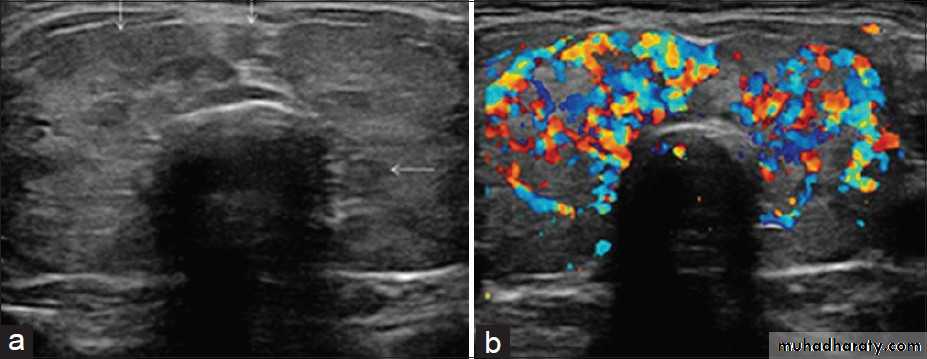

• Ultrasound: enlarged, hypoechoic and hypervascular thyroid.

Diagnosis is often achieved by clinical history and examination, plus laboratory tests for thyroid function and antibodies. These may be complemented by thyroid scintigraphy with 99mTc, and US with color Doppler.